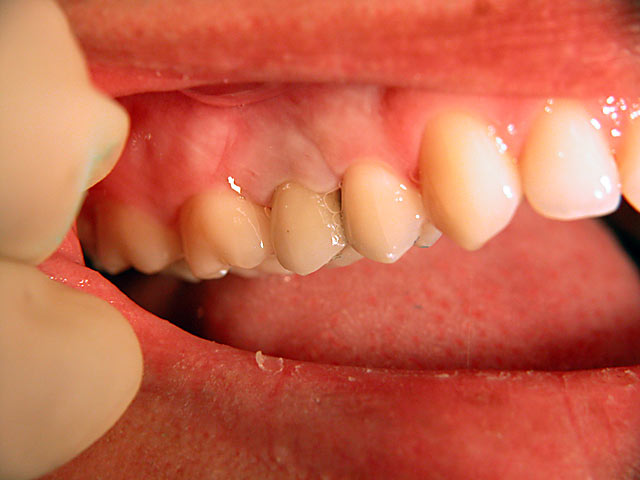

Die folgenden Patientenfälle sollen Ihnen einen Einblick in die Möglichkeiten der modernen Implantation geben.